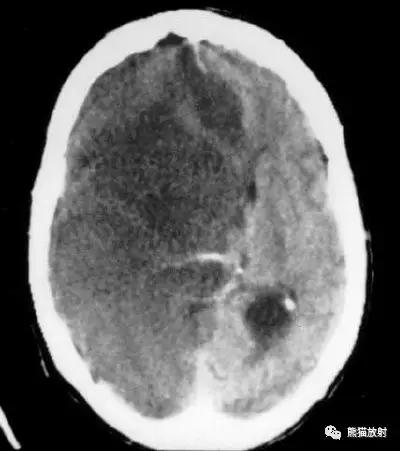

出血性脑梗死

上矢状窦血栓形成,呈高密度(箭头);并邻近脑实质内出血性脑梗死。